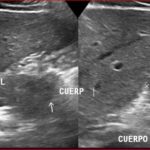

Paciente masculino de 35 años de edad, con antecedentes de tabaquismo, etilismo, consumo de sustancias psicoactivas. Ingresa al hospital de Sanatorio Franchin el 24 de mayo de 2024, donde se constata hipoglucemia severa con buena respuesta al glucosado hipertónico endovenoso. Al examen físico con la típica tríada de Whipple, dado por síntomas neuroglucopénicos de alteración del estado de conciencia, glucemia de 25 mg/dl y alivio sintomático después de la administración de glucosa. El paciente recupera el estado de conciencia y refiere dolor abdominal a nivel de epigastrio, por lo que se le realiza ecografía abdominal, donde se evidencia lesión nodular hipoecogénica en cuerpo del páncreas. Por esta razón se pasa al paciente a tomografía, donde se constata una formación nodular a nivel del cuerpo del páncreas, que presenta un ávido realce en fase arterial con homogeneización de la lesión en tiempo tardío.

Una vez que tengamos una fuerte sospecha diagnóstica basada en la clínica y el laboratorio bioquímico viene la localización del tumor, que se puede realizar a través de métodos no invasivos, como la ecografía, que como método de abordaje inicial no está mal para una primera exploración, pero debemos conocer que su sensibilidad es muy baja, del 9%. Pero como un estudio no invasivo, rápido, relativamente económico, y si está disponible en nuestro servicio, se puede utilizar. Los insulinomas se pueden observar por este método como una imagen nodular hipoecogénica que puede mostrar ante la presencia de Doppler color un patrón periférico o centrípeto, porque recordemos que estos son tumores hipervasculares, lo que significa que tienen una alta densidad de vasos sanguíneos.

Para mi caso, y dando una visión general de los métodos de imagen no invasivos en esta revisión retrospectiva, solo a uno de los pacientes se le detectó la lesión por ecografía, donde se visualizó una lesión nodular hipoecogénica en el cuerpo del páncreas. A los demás pacientes se les detectó la lesión por tomografía en estudio trifásico, donde resaltan las características ya descritas por la literatura de lesiones hipervasculares con intenso realce en fase arterial, localizadas en diferentes partes del páncreas, como cabeza, cuerpo y cola.